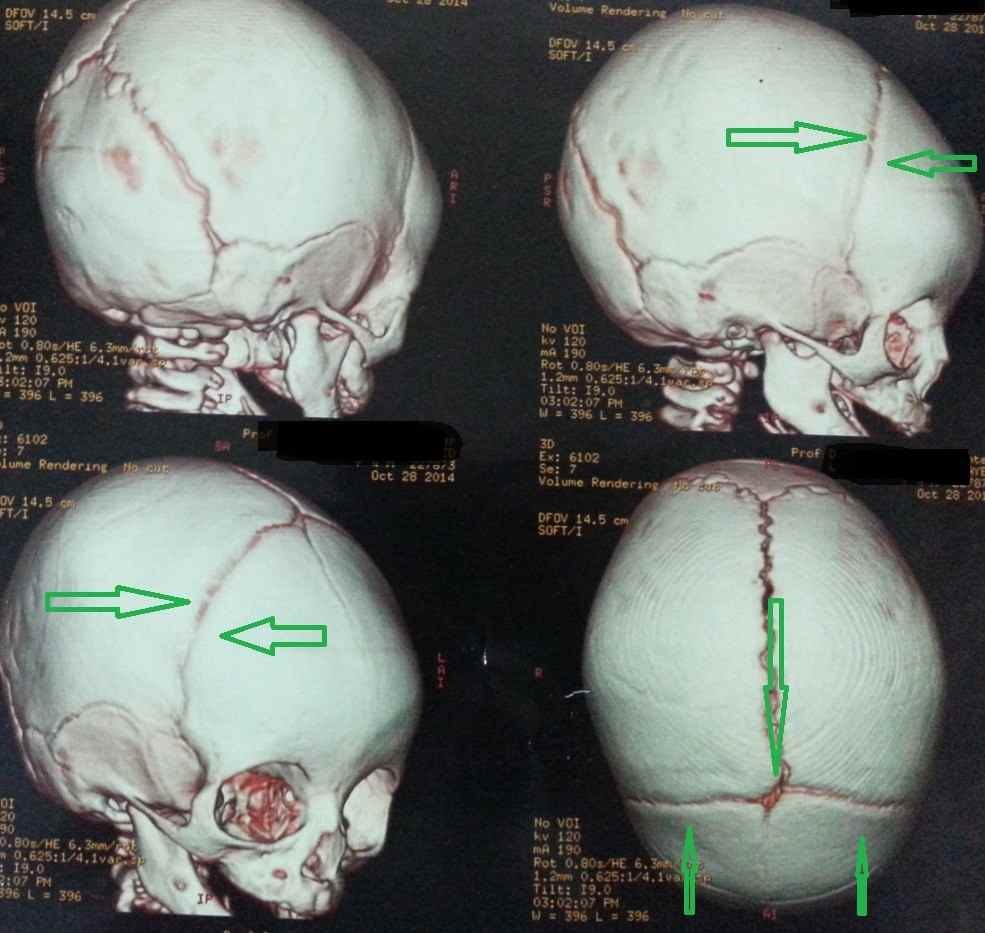

طفلة اربع شهور محولة من استشاري الاطفال بسبب البكاء المستمر الغير مبرر المصحوب بنوبات قئ وبعد توقيع الكشف لوحظ تفلطح او قصر الجبهه وبعمل اشعة ثلاثية الابعاد ومقطعية علي المخ وجد بها انسداد مبكر للدروز الاكليلية الجبهية بالجهتين اليمني واليسري مع انغلاق جزئى لليافوخ الامامي. وتم اجراء جراحة لتفتيح الدروز المنغلقة ثم متابعة الطفلة حتي اخر زيارة وهي بنت اربع اعوام بحالة ذهنية ممتازة.